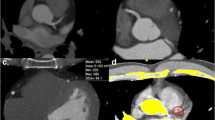

An example of the automatic CAC assessment on contrast CTA with corresponding non-contrast CT reference is depicted in Fig. 2.

Patient example of coronary calcium detection with both methods. A 66 year old male patient with calcified coronary plaque in the LAD. a Illustrates the coronary artery calcium (CAC) on the non-contrast CT scan (arrows). b Depicts the manual detection of the calcified lesions on the same non-contrast CT scan. c CAC in the same patient on the contrast CTA scan. d Depicts the automatic detection and quantification of the calcium on the contrast CTA scan with a novel fully automatic algorithm. The Agatston CAC score was 63 on the non-contrast CT scan and 58 on the contrast CTA scan as assessed with the fully automatic algorithm